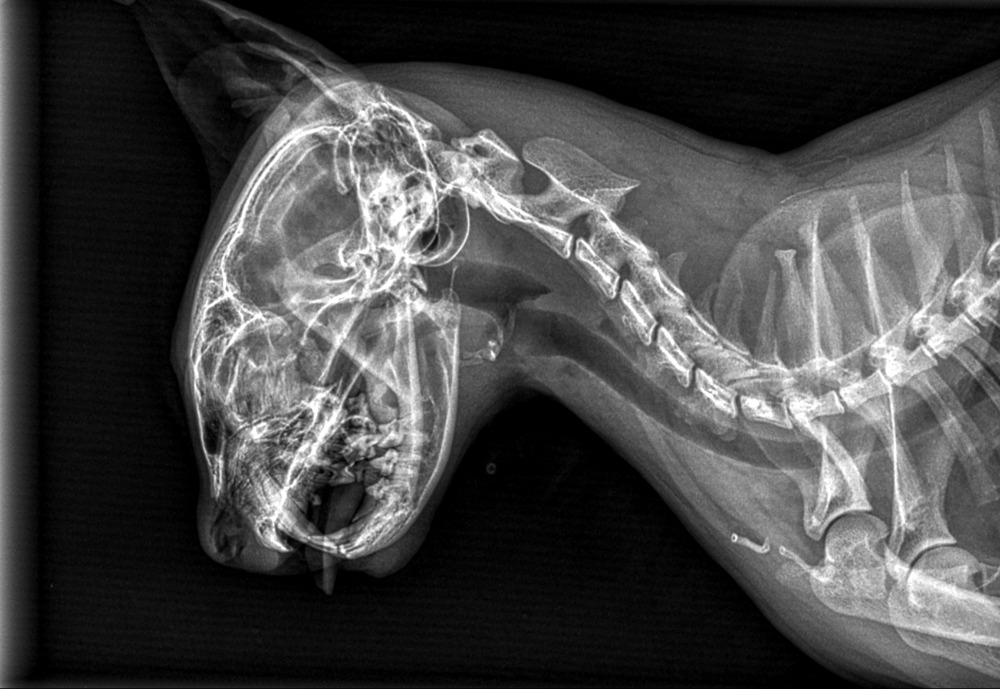

Bravecto, známé především jako žvýkací tableta je nyní dostupné i v injekční formě a poskytuje až 12 měsíců ochrany proti klíšťatům a blechám – jedinou aplikací u veterináře. Bravecto injekční je určeno pro psy od 6 měsíců věku s ustálenou hmotností. Obsahuje inovativní suspenzi krystalů účinné látky fluralaneru, která se po aplikaci do podkoží...